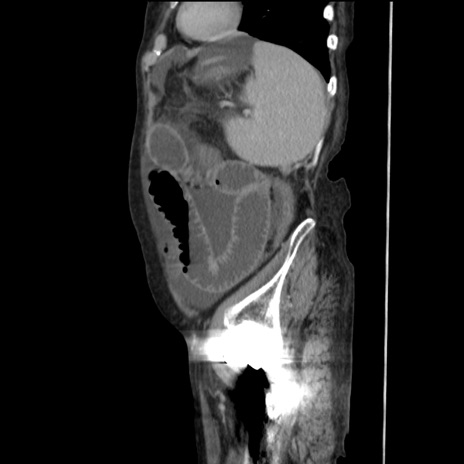

症例31(矢状断像)

【症例】80歳代 女性

【主訴】腹部膨満感

【現病歴】他院にて肝硬変にてフォロー中。1週間前から便秘、腹部膨満感、臍部腫瘤あり受診となる。

【既往歴】肝硬変

【身体所見】腹部膨隆あり、皮膚変化なし、疼痛なし。

【データ】WBC 4600、CRP 0.25